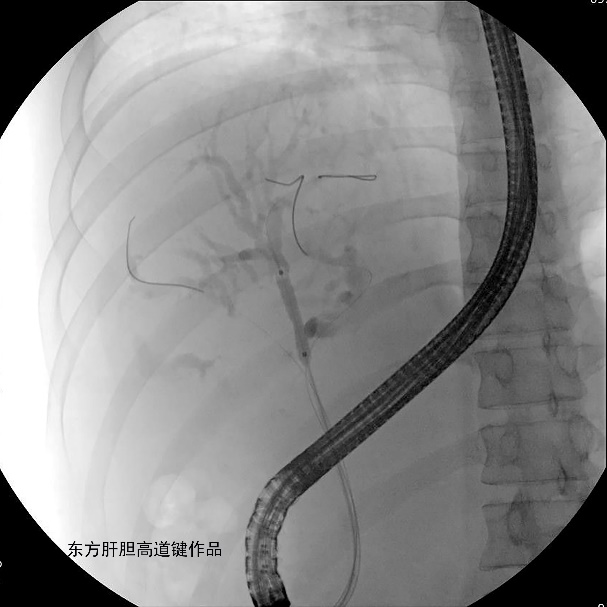

图A:胆总管造影见胆总管未见异常,肝门胆管细线样狭窄,累及肝总管、分叉、右前、左内及左外肝内胆管,各胆管分支间通而不畅;

图B:两根导丝分别超选进入右前及左内肝内胆管;左右肝内胆管各抽得白胆汁5ml与15ml,标本送培养;